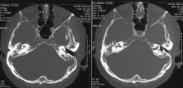

中耳癌為發生于中耳的少見惡性癌腫,多為原發。中耳癌的誘因,很可能是中耳的長期感染,據統計,多數中耳癌患者有慢性化膿性中耳炎的病史。其發病年齡多為40~60歲,本病病理是以鱗狀上皮細胞癌最常見,基底細胞癌和腺癌在中耳很少見。